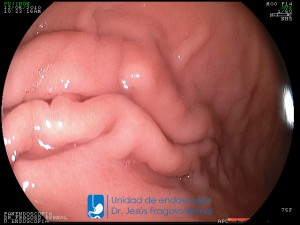

La Unidad de Endoscopía fue creada en 2002 por el Dr. Jesús Fragoso Bernal, es pionera en el estado por la utilización de la tecnología más avanzada, que nos permite ofrecer servicios integrales de diagnóstico y tratamiento para las enfermedades del aparato digestivo.

El profesionalismo de nuestro personal, altamente especializado, se distingue por la calidad y calidez de nuestros servicios con el objetivo de brindar una atención de excelencia en el ambiente más confortable para comodidad y seguridad de nuestros pacientes.

"La Unidad de Endoscopía se ha caracterizado por un progreso continuo desde su inicio marcando la pauta en los procedimientos endoscópicos en el estado de Tlaxcala y estando siempre a la vanguardia tecnológica."

Dr. Jesús Fragoso Bernal